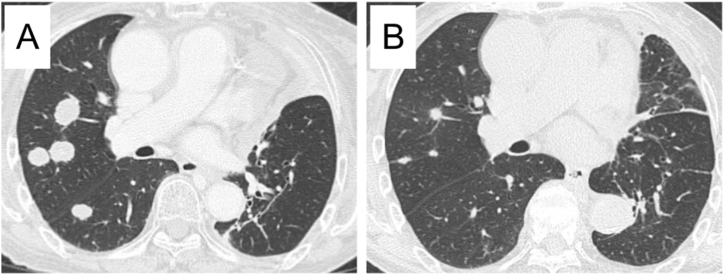

Fig. 3.

Chest computed tomography findings. Images before the administration of osimertinib showed enlarged metastatic colonies predominantly in the right lung (A). After two months of osimertinib treatment, the metastatic colonies had obviously shrunk (B).

When we started the second-line chemotherapy, we also performed F1CDx using the biopsied specimen at the diagnosis. Surprisingly, it detected a rare variant of EGFR exon19 deletion (S752_I759del) that was not covered by the ODxTT. Although we administered S-1 for three cycles, the metastatic nodules in her right lower lung field grew (Fig. 1C). We then treated her with osimertinib (80 mg daily), a third-generation EGFR-TKI. She showed a favorable anti-tumor response here (partial response according to the Response Evaluation Criteria in Solid Tumors [RECIST] v1.1) (Figs. 1D, and Fig. 3), and the response has continued for six months since the administration of osimertinib.